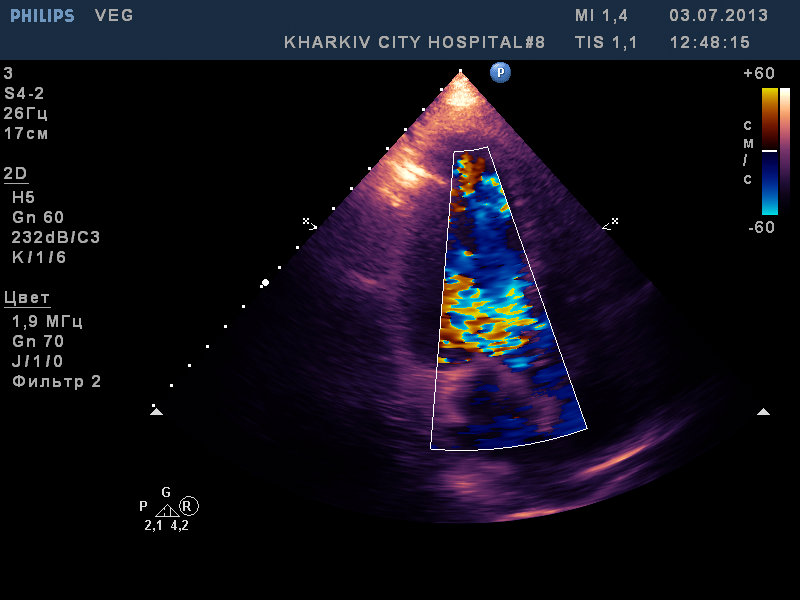

вегетации на АК, МК и ТК

молодой 37лет, с гепатитом C, возможно имеет место быть ВИЧ. по виду наркоман с конкретным стажем